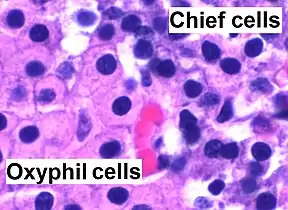

Microanatomy

The parathyroid glands are named for their proximity to the thyroid—and serve a completely different role than the thyroid gland. The parathyroid glands are quite easily recognizable from the thyroid as they have densely packed cells, in contrast with the follicular structure of the thyroid.[6] Two unique types of cells are present in the parathyroid gland:

- Chief cells, which synthesize and release parathyroid hormone. These cells are small, and appear dark when loaded with parathyroid hormone, and clear when the hormone has been secreted, or in their resting state.[7]

- Oxyphil cells, which are lighter in appearance and increase in number with age,[7] have an unknown function.[8]

Intermediate magnification micrograph. H&E stain. The white round structures are fat cells. Adipose tissue comprises 25–40% of normal parathyroid gland tissue.[7] High magnification micrograph. H&E stain. The small, dark cells are chief cells, which are responsible for secreting parathyroid hormone. The cells with orange/pink staining cytoplasm are oxyphil cells

High magnification micrograph. H&E stain. The small, dark cells are chief cells, which are responsible for secreting parathyroid hormone. The cells with orange/pink staining cytoplasm are oxyphil cells